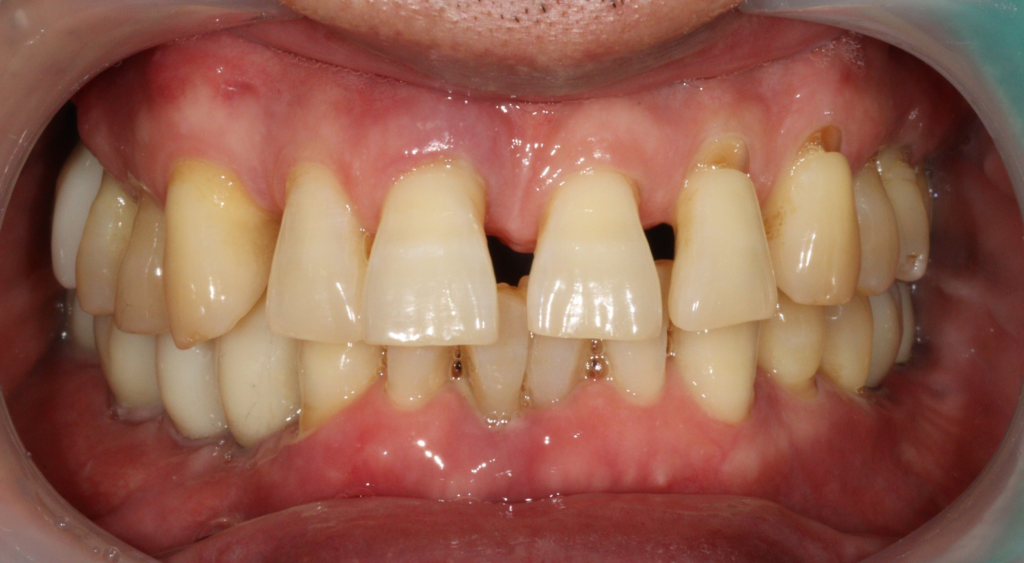

시술 전

25.06.10

해당 환자분께서는 여러 가지 구강 문제로 내원하셨습니다.

먼저 비교적 젊은 연령대임에도 불구하고 상악 치아 사이가 벌어지는 증상이 나타나면서 심미적인 부분에서 불편함을 느끼고 계셨습니다. 웃을 때 보이는 전치부의 변화가 신경 쓰여 상담을 원하셨습니다. 또한 하악 전치부에서는 치아의 동요가 관찰되었습니다. 보다 정밀한 상태를 확인하기 위해 방사선 검사를 진행한 결과, 기존에 임플란트가 식립되어 있던 부위 앞쪽 치아 주변에서 치조골이 상당 부분 소실된 모습이 확인되었습니다.

이에 따라 부위별로 다른 치료 계획을 세우게 되었습니다. 상악 전치부의 경우에는 환자분과 충분한 상담을 진행한 뒤, 심미적인 결과를 우선적으로 고려하여 보철 치료를 통해 전치부를 회복하는 방향으로 계획을 수립했습니다. 자연스러운 치아 형태와 배열을 고려하여 보철물을 제작하는 방식으로 진행하기로 하였습니다.

반면 하악 전치부는 기능적인 문제와 함께 심미적인 요소도 중요한 부위이기 때문에, 염증의 범위가 심하지 않은 경우에는 발치 후 즉시 임플란트 식립을 고려하는 치료 계획을 세웠습니다. 정확한 상태를 평가한 뒤 발치와 동시에 식립이 가능한지 여부를 판단하여 진행하기로 하였습니다.